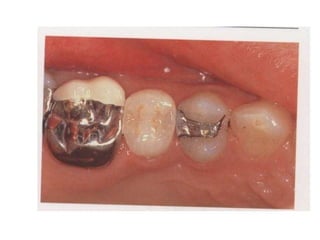

Bridge: (fixed prosthesis)

(fixed partial denture): is a non

movable prosthesis which is

rigidly attached to one or more

abutment teeth to replace one or

more lost missing teeth.

Component Parts of bridge

Abutment tooth Retainer

Pontic

Connector

* Fixed fixed bridge: is a

bridge where the retainer and

pontic s are all solder together

and the bridge is cemented at

both ends to the abutment teeth.